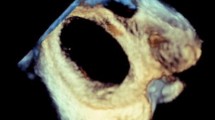

Once the left side of the atrial septum has been acquired, a rightward tilting of the volume will show the right side of the atrial septum and the fossa ovalis as a depression on the septum. In some cases, fine cropping using the arbitrary crop plane was necessary to remove the surrounding atrial structures obscuring the septum. A gain setting at medium level was required to avoid the disappearance of the fossa ovalis and creating a false impression of an ASD (Fig. 1).

For 3D TTE image acquisition, we used the 3D zoom prepare in the sub-coastal window, bicaval view then the volume was oriented to view the IAS from the RA with the SVC located at the 11-o’clock position (Fig. 2).

In terms of data analysis, after adjusting the sector aiming for the septum to be in the “en face view”, excluding possibility of oblique view, the defect area and circumference were measured by ball tracking the defect, the defect shape, position and 2 dimensions were documented in the 3D image.